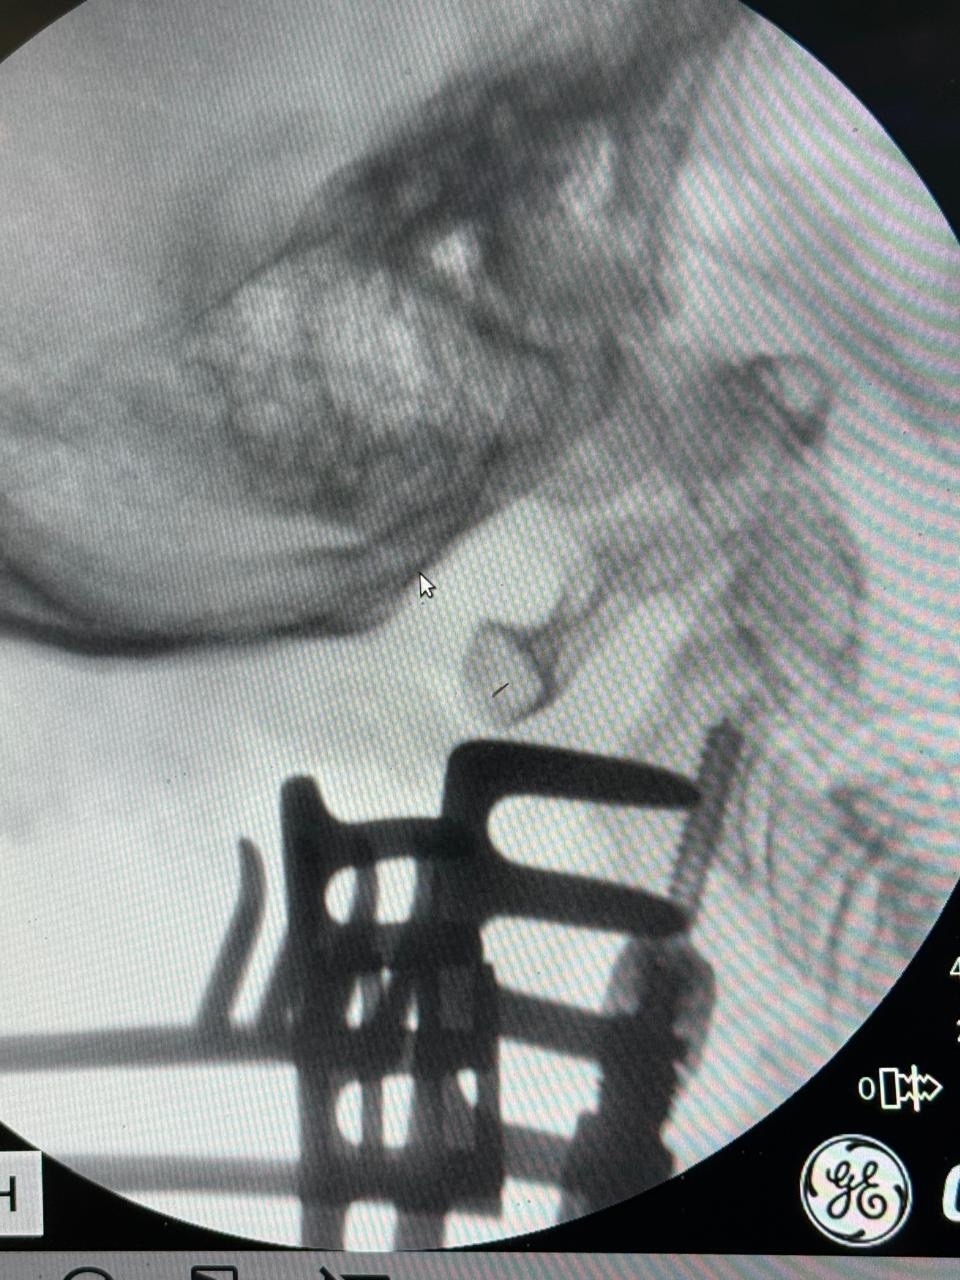

"76-летняя поступила в отделение с перелом зуба осевого позвонка (С2) типа Anderson D’Alonzo II со смещением. Такая травма, полученная в быту, крайне нестабильна и чревата риском повреждения спинного мозга на уровне ствола головного мозга с развитием мгновенного паралича или летального исхода. Консервативное лечение (ношение жесткого воротника) в данном случае было признано недостаточно эффективным из-за высокого риска несращения и постоянной угрозы для жизни. Было принято решение о проведении операции по методике Хармса. Раньше "золотым стандартом" при таких переломах была операция по методике Magerl — транспедикулярная фиксация С1-С2. Однако она технически сложна и сопряжена с риском повреждения позвоночной артерии. Пациентка была выписана в удовлетворительном состоянии под амбулаторное наблюдение. Прогноз — благоприятный, с полным восстановлением качества жизни" - поделился врач-нейрохирург Мухиддин Тохтаров.